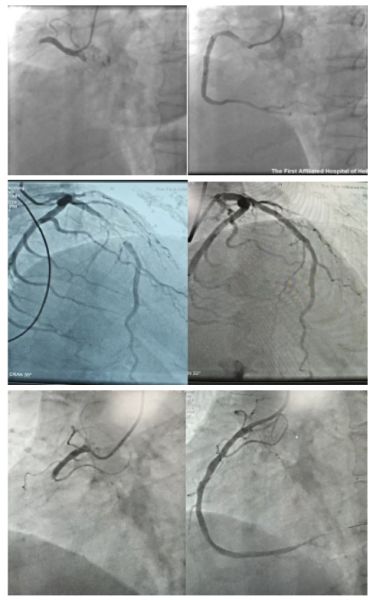

手术中,科室医护团队展现出高超的介入技术和丰富的应急处理能力。医生通过桡动脉穿刺,将细小的导丝和球囊导管精准送达堵塞的冠状动脉处,随后利用球囊扩张并植入支架,从而迅速开通闭塞的血管,恢复了心脏血液供应。手术过程顺利,术后患者胸痛症状迅速缓解,生命体征趋于平稳。同时,科室医护团队在围手术期管理中充分发挥中西医结合的治疗特色,在规范的西药治疗基础上,根据每位患者的具体证型,配合中药汤剂、穴位贴敷等特色疗法,达到益气活血、温阳通脉的效果,有效改善患者的心功能,减轻心肌再灌注损伤,以及心悸、失眠等术后不适,促进患者恢复,显示出中医药在急危重症救治中的独特优势。